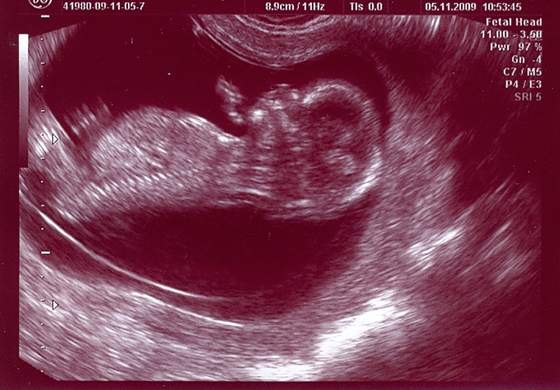

a musze przyznać, że jak robiłam te badania, to mieli lepszy sprzęt i mam śliczne zdjęcie z tego badania:-)

zdjęcie z usg prenatalnego cos koło 11 tygodnia...